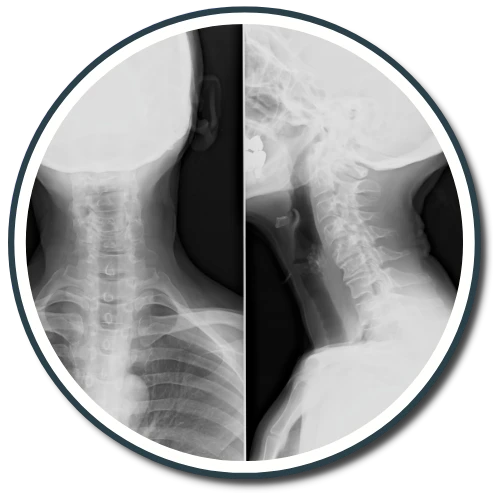

The Gonstead Technique relies on five essential components: Visualization, Instrumentation, Palpation, X-Ray, and patient symptoms. By integrating these elements, we can pinpoint the precise location that requires adjustment. When all these factors align, we can provide the patient with a specific and effective adjustment. Specificity is the key, as Dr. Gonstead emphasized that three adjustments on the wrong vertebral segment could lead to a Subluxation, highlighting the importance of precision.

According to the Gonstead methodology, understanding that subluxations originate from the disc is crucial. Recognizing the stages of disc degeneration is essential for determining the appropriate adjustment direction and force needed for effective correction.

Dr. Gonstead's Level Disc Theory asserts that "anatomically and physiologically normal discs promote optimum vertebral alignment." This is evidenced when the vertical height of a vertebral couple is uniform around 360 degrees, with the vertebral bodies properly aligned. This alignment, known as "Parallel Discs," ensures even weight distribution, adequate nutrient flow, and optimal joint function and movement within the spine.